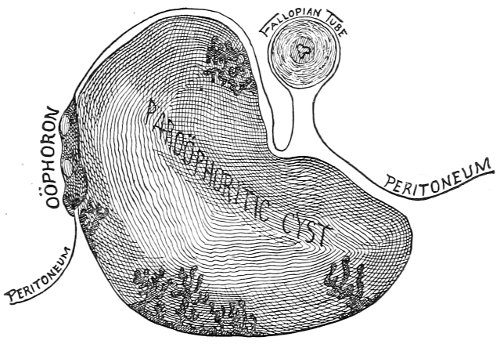

The origin of vaginal cysts has been much disputed. It is probable that they arise from the remains of the Wolffian canal—the canal of Gärtner. In the embryo the transverse or longitudinal tubule of the parovarium extends to the side of the uterus and thence down the side of the vagina to the urethral orifice. It persists in this condition in some of the lower animals—the sow and the cow—and may also persist as a closed tube in woman. In such cases it may become distended and form the vaginal cyst.